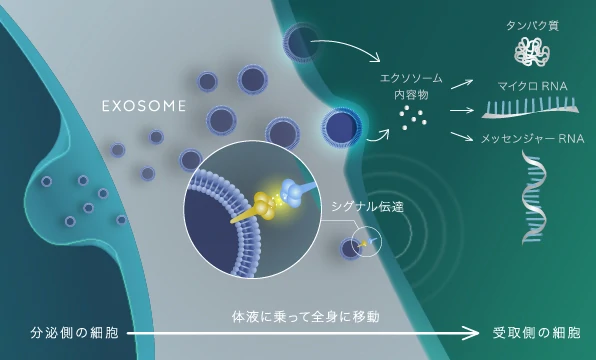

近年、再生医療の主役は「生きた幹細胞の移植」から、幹細胞が分泌する情報伝達物質「エクソソーム(細胞外小胞)」へと完全にパラダイムシフトを遂げました。

エクソソームとは、直径わずか30~150nm程度の極小のカプセルです。内部にはmiRNA(マイクロRNA)やタンパク質などの生理活性分子が高密度に充填されており、生体内を巡って細胞から細胞へと「若返りと修復のプログラム」を届けるメッセンジャーとして機能します。

加齢やストレスで傷ついた細胞に対し、エクソソームが「炎症を止めよ」「組織を再生せよ」という正確な遺伝子指令(コード)を渡すことで、損傷した細胞の運命を劇的に転換させます。生きた細胞を含まないため腫瘍化のリスクがなく、極めて高い安全性を誇るのが特徴です。

このエクソソームを点滴で全身の血管に行き渡らせることで、抗炎症・抗酸化作用が働き、全身の機能回復、脳の若返り、肌や髪の再生など、複合的なアンチエイジング効果がもたらされます。

表面のひび割れを塗って誤魔化すのではなく、建物の土台に潜り込み、最高級の素材を用いて根本からの修復を目指す「熟練の修復師」のように。エクソソームは細胞間のメッセンジャーとして働き、老化した組織の運命を劇的に転換させる力を秘めています。